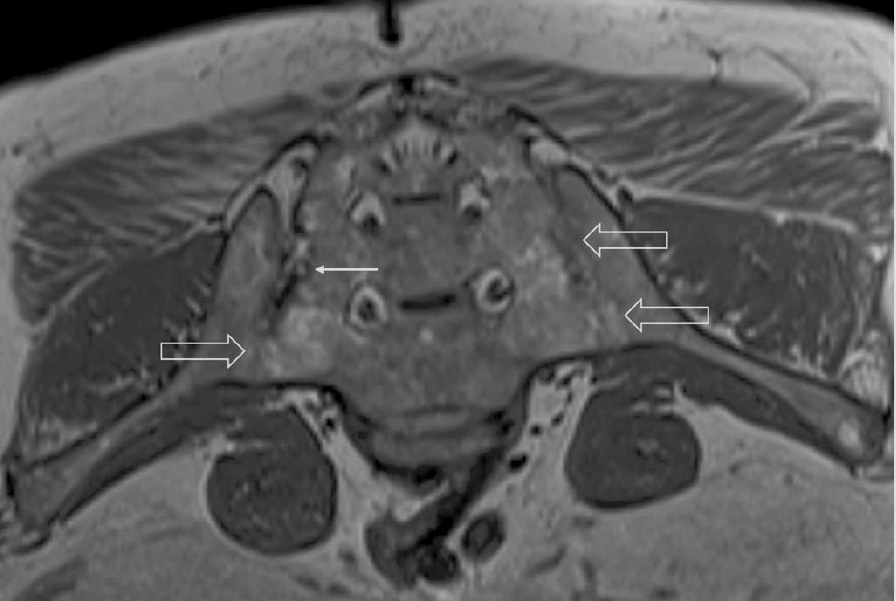

При компьютерной томографии органов грудной клетки данных за «свежие» очаговые и инфильтративные изменения не получено. Увеличения лимфатических узлов подмышечных областей, средостения, корней легких не выявлено. Отмечался усиленный грудной кифоз, обызвествление передней продольной связки, на всем уровне исследования определялись передне-боковые спондилофиты, а также анкилоз большинства реберно-поперечных суставов. По данным рентгенографии кистей (рис. 1, 2) и стоп (рис. 3, 4) диагностированы признаки эрозивного артрита, анкилоз суставов запястья. По данным МРТ крестцово-подвздошных суставов (КПС) определялся неравномерный анкилоз КПС, хрящи по суставным поверхностям неравномерной толщины, примерно на половине протяжении сустава отсутствуют, «суставной промежуток» облитерирован. Неравномерность и нечеткость контура суставных поверхностей за счет множества краевых эрозий справа, единичных – слева, с наличием остеокластоза, в нижнем отделе слева по смежным отделам определяются участки трабекулярного отека, данная находка клинически интерпретирована как двусторонний активный сакроилиит (рис. 5, 6).

Рис. 5. Магнитно-резонансная томография (Т2-взвешенное изображение в поперечной проекции). Протяженные участки анкилоза крестцово-подвздошных сочленений (толстые стрелки), эрозии суставных поверхностей (тонкие стрелки)

Рис. 6. Магнитно-резонансная томография (Т1-взвешенное изображение в косой корональной проекции). Протяженные участки анкилоза крестцово-подвздошных суставов (толстые стрелки), субхондральная киста правой латеральной массы крестца (тонкая стрелка). При магнитно-резонансной томографии крестцово-подвздошных сочленений с обеих сторон определяются крупные зоны анкилоза (суставные щели полностью облитерированы на 1/3 поверхности сустава справа, на 2/3 поверхности слева, что соответствует III рентгенологической стадии сакроилиита справа, IV стадии слева по Келлгрену). На остальных участках суставной хрящ неравномерно истончен, суставные поверхности неровные за счет множественных эрозий справа, единичных – слева. Определяются единичные мелкие (4 мм) субхондральные кисты справа